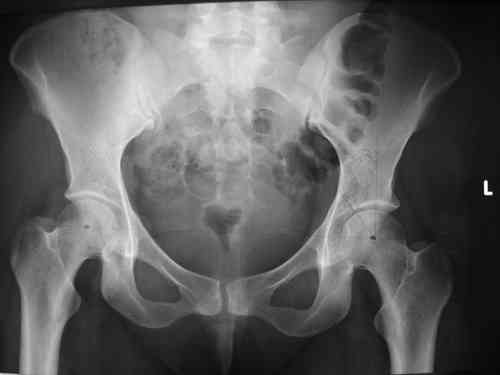

прилагаю пример с такой же давностью травмы, репонировали аппаратом

> в аппарате или одномоментно открыто. Лично я склоняюсь к аппаратному лечению на первом этапе.

задача непростая, если мало опыта в этом деле, подумайте еще раз